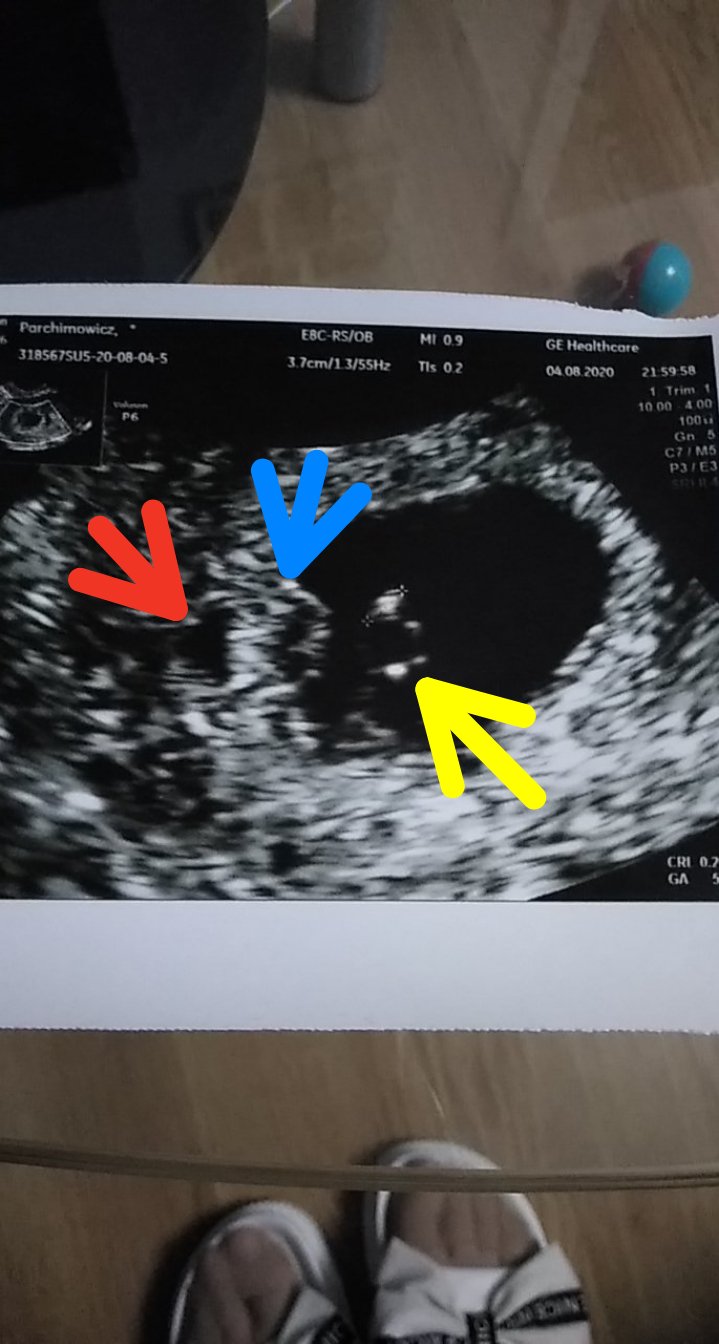

To jestem po usg i moja kruszynka ma się super! :D <3 :) serduszko pięknie bije, wszystko tak jak powinno być, tylko po bokach pęcherzyka są takie dwa wybrzuszenia i lekarz powiedział, że nie ma pojęcia co to jest, bo pierwszy raz coś takiego widzi xD powiedział, że to nic niepokojącego, ale powiem wam, że jak zobaczyłam na początku 3 kulki w tym pęcherzyku to prawie z fotela zjechałam xD mam przyjść za 2 tygodnie :) nie wiem teraz, czy zostać z wami, bo z usg wychodzi, że to 5t + 6d i termin porodu na 31.03.2021 :p :) :D

Nie dają mi spokoju te wybrzuszenia, a raczej wygląda to tak jakby tam był jeszczw jeden malutki pęcherzyk

Żółte zarodek

Czerwone jakby drugi pęcherzyk

Niebieskie niewiadomo co to jest :p

No właśnie chyba tak tylko wygląda na to, że drugi zarodek chyba się nie rozwinął, bo skoro jedno serduszko dzisiaj było to drugie też powinno być

Koleżanka ma bliźniaczki i dowiedziała sie na drugiej wizycie. Na pierwszej słychać było tylko jedno serduszko, wiec ginekolog czekał do następnej wizyty jak sie rozwinie sprawa z drugim pęcherzykiem i na kolejnej wizycie biło juz drugie serduszko😉 także kto wie... może nosisz w sobie podwójne szczęście😁